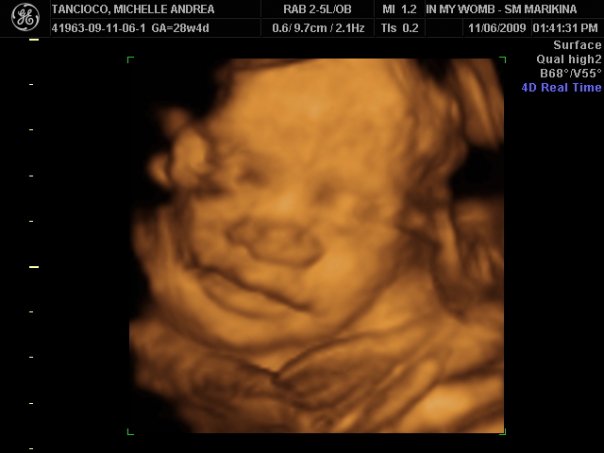

Hanz And Calleigh S World 2009